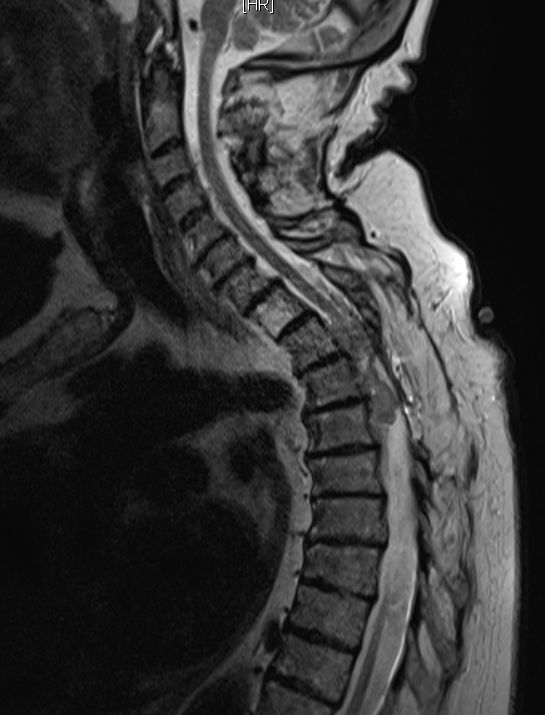

| Rückenmark |

76-jährige Frau mit Rezidiv eines Rückenmarks-Meningeoms. Erstmanifestation vor 17 Jahren. Rezidive von 12, 6 und 3 Jahren jeweils operativ beherrscht. Seit einem Jahr erneut Schmerzen zwischen den Schulterblättern und Druckgefühl im Thoraxbereich. Reduzierter AZ und adipöser EZ. KHK, VHF, Hypertonie, Hypothyreose. Auf Rollator angewiesen. Zunehmende Gangunsicherheit und Kribbeln in den Beinen. Klopfschmerz im Bereich von BWK2-5 stark auslösbar. Die Schmerzen strahlen zeitweise in die Schulterblätter aus. | ![]() | |||||

![]() |

![]() | ||||||